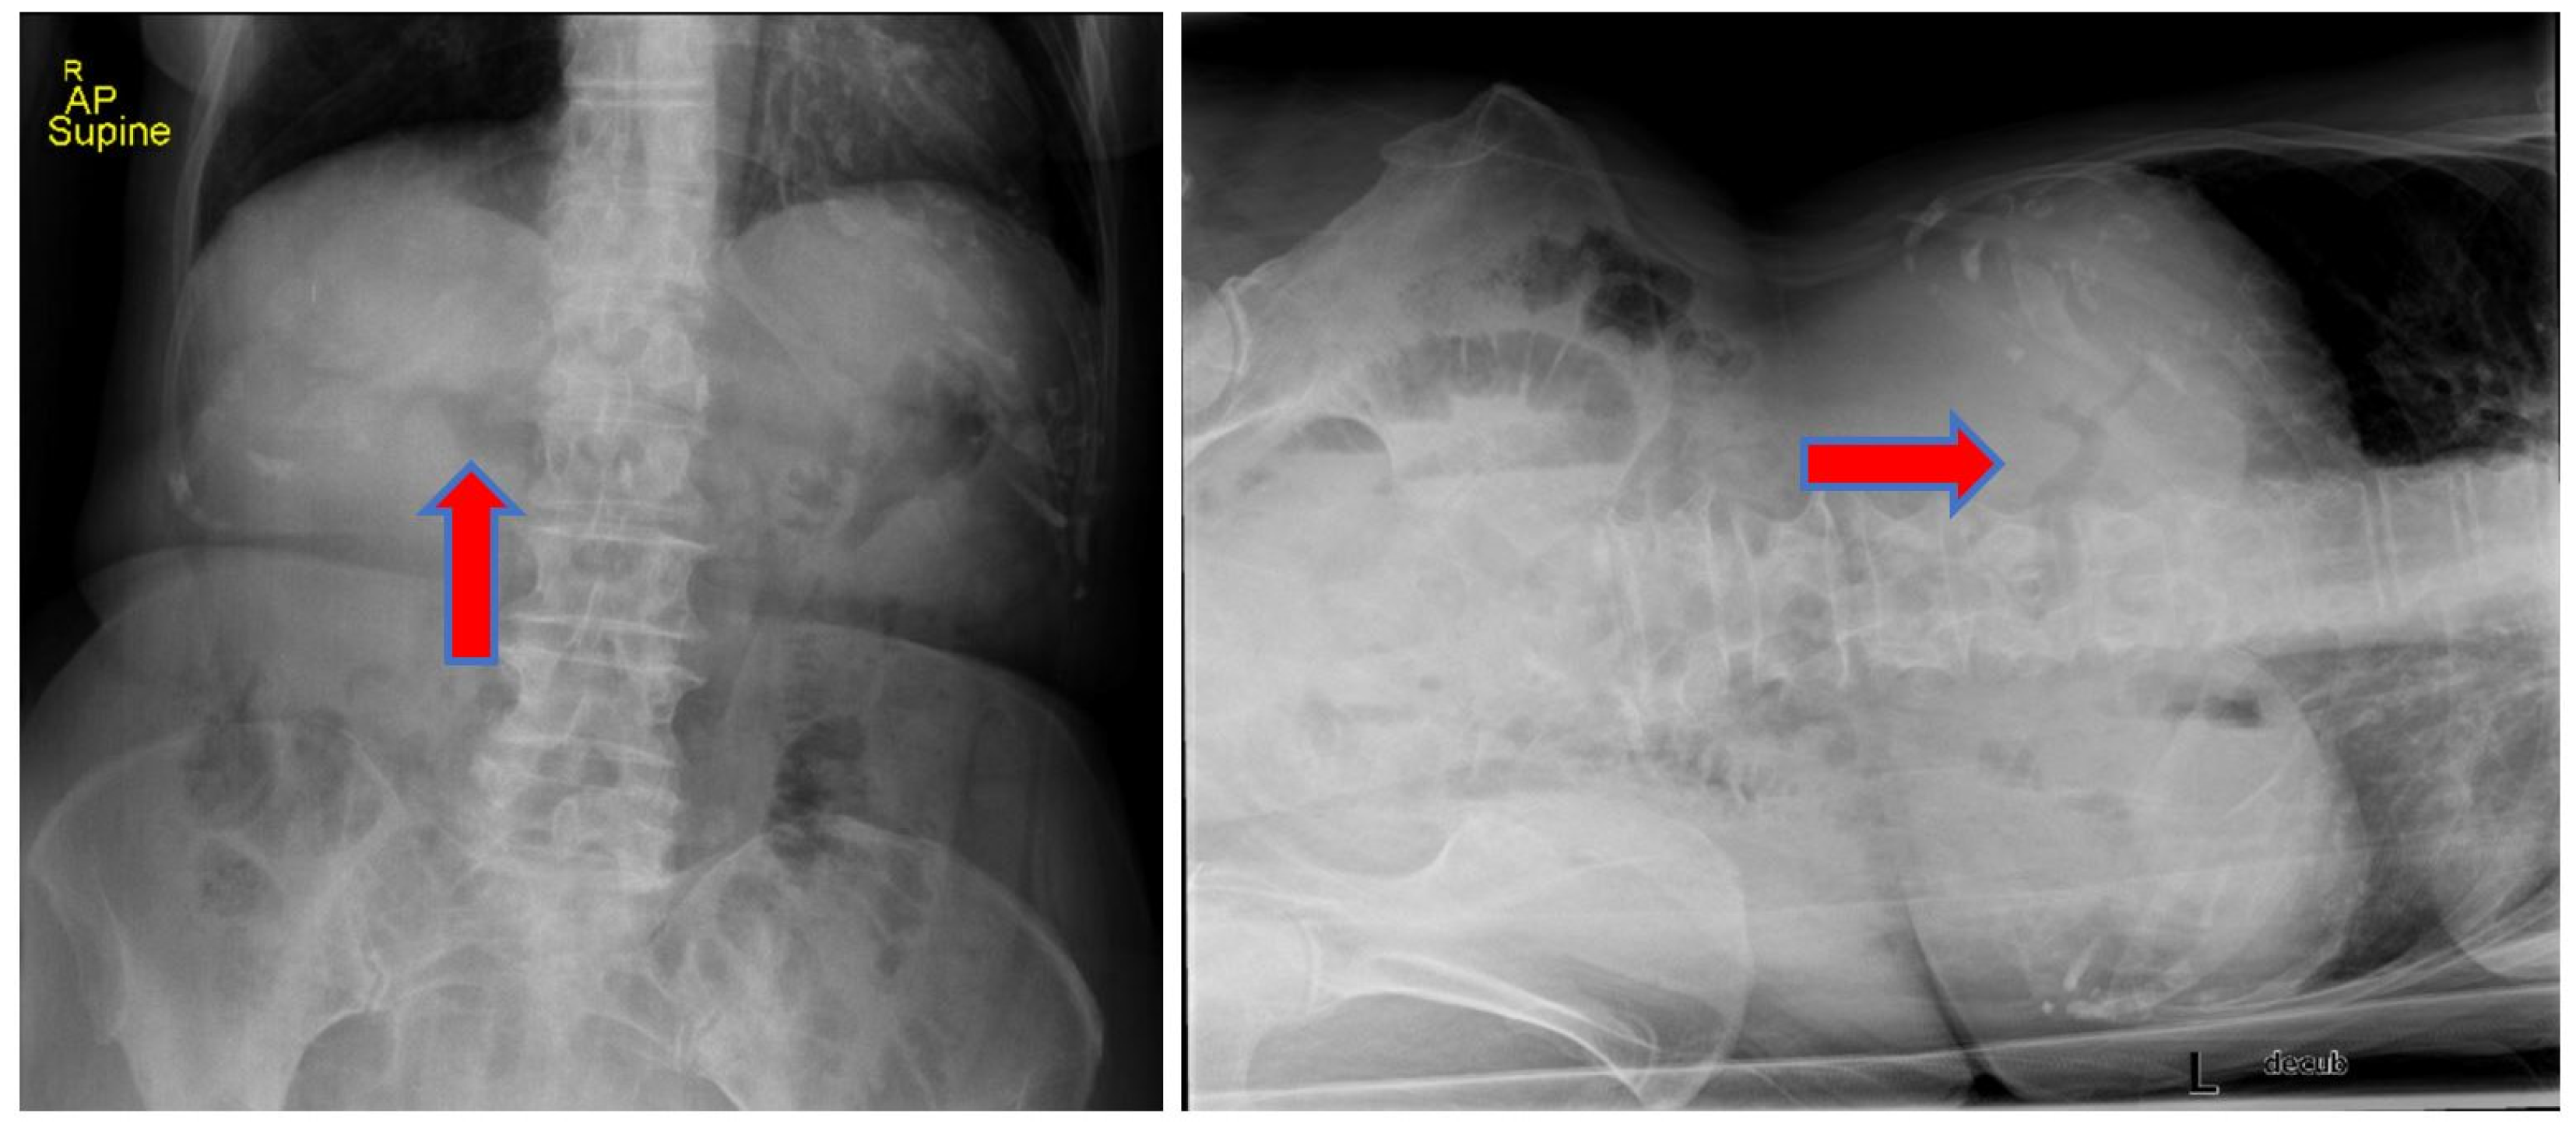

We report the case of an 83-year-old woman who presented to our emergency department (ED) with progressive worsening abdominal pain, nausea, and non-bloody, bilious emesis of one day’s duration that continued overnight in the ED. Her medical history includes coronary artery disease status following angioplasty and stenting, in addition to choledocholithiasis with acute cholangitis requiring endoscopic retrograde cholangiopancreatography (ERCP) with sphincterotomy and percutaneous transhepatic biliary drainage (PTCD) approximately one year prior in her home country, Scotland. Regrettably, the patient’s PTCD tube became dislodged, and she began to develop severe abdominal pain, prompting presentation to our facility. There was no recent history of fever, jaundice, acholic stools, or dark urine. A two-view abdominal radiograph was initially obtained showing a branching density over the liver relating to portal venous gas (

Figure 1). Computerized tomography (CT) of her abdomen showed circumferential mid-jejunum bowel wall thickening with a mildly dilated bowel proximally, prominent mesenteric edema, mild intra- and extrahepatic biliary ductal dilatation with pneumobilia, perigastric inflammation, a contracted gallbladder, and probable obstructing mass in the first portion of the duodenum (